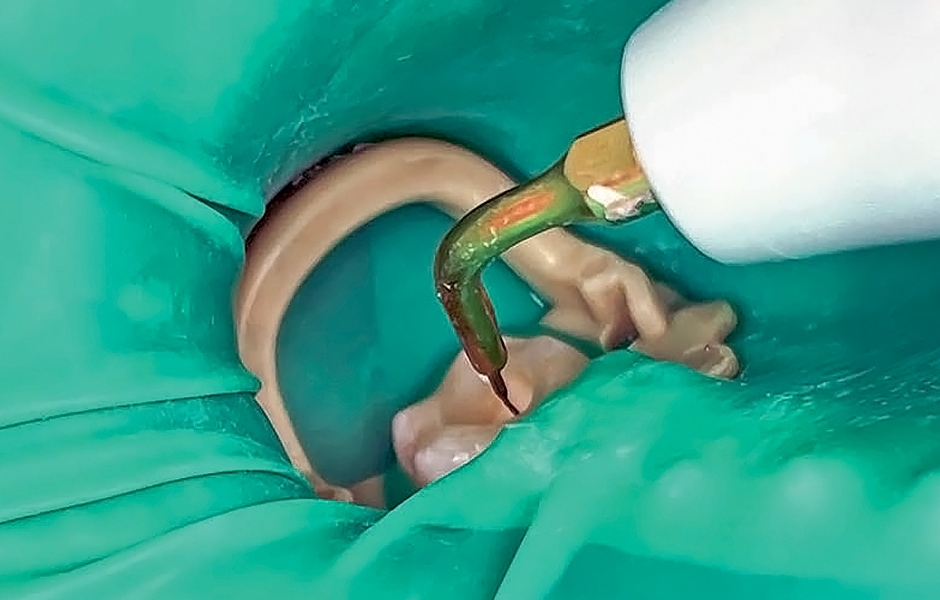

Postižené kanálky byly nejprve preparovány pomocí ručního nástroje na požadovanou velikost 20. Poté následoval protokol elektrochemické irigace pomocí ultrazvukového hrotu (obr. 3): Klasická sekvence chlornanu sodného, EDTA, chlornanu sodného a 0,2% chlorhexidinu k dezinfekci kanálků podpořila účinné odstranění zbytků tkání a nečistot. Do vyčištěných kanálků byl aplikován hydroxid vápenatý fixovaný PTFE páskou a zub byl provizorně uzavřen materiálem DuoTEMP (COLTENE). Před vyleštěním dočasné výplně byla zkontrolována okluze a pacientka byla propuštěna – až do další návštěvy se u ní neprojevily žádné nežádoucí příznaky.

Obr. 3: Ultrazvukově aktivovaná irigace.